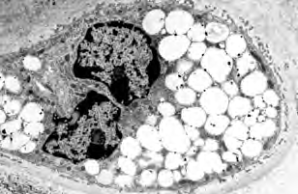

Project 6: Molecular analysis of the bidirectional crosstalk between bone and lipid metabolism

Project 6 aims to identify metabolites that are released by osteoblasts and possibly regulate bone and systemic metabolism as signalling molecules. The relevance and specificity of the changes will be investigated in genetic models in order to explore new therapeutic options for the treatment of patients with low bone mineral density.